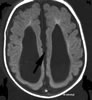

Korpus kallozum

Beyin iplik demeti,beyin köprüsü. Memeli hayvanlarda iki beyin yarı küresini birleştiren büyük komissür fibril demetidir.